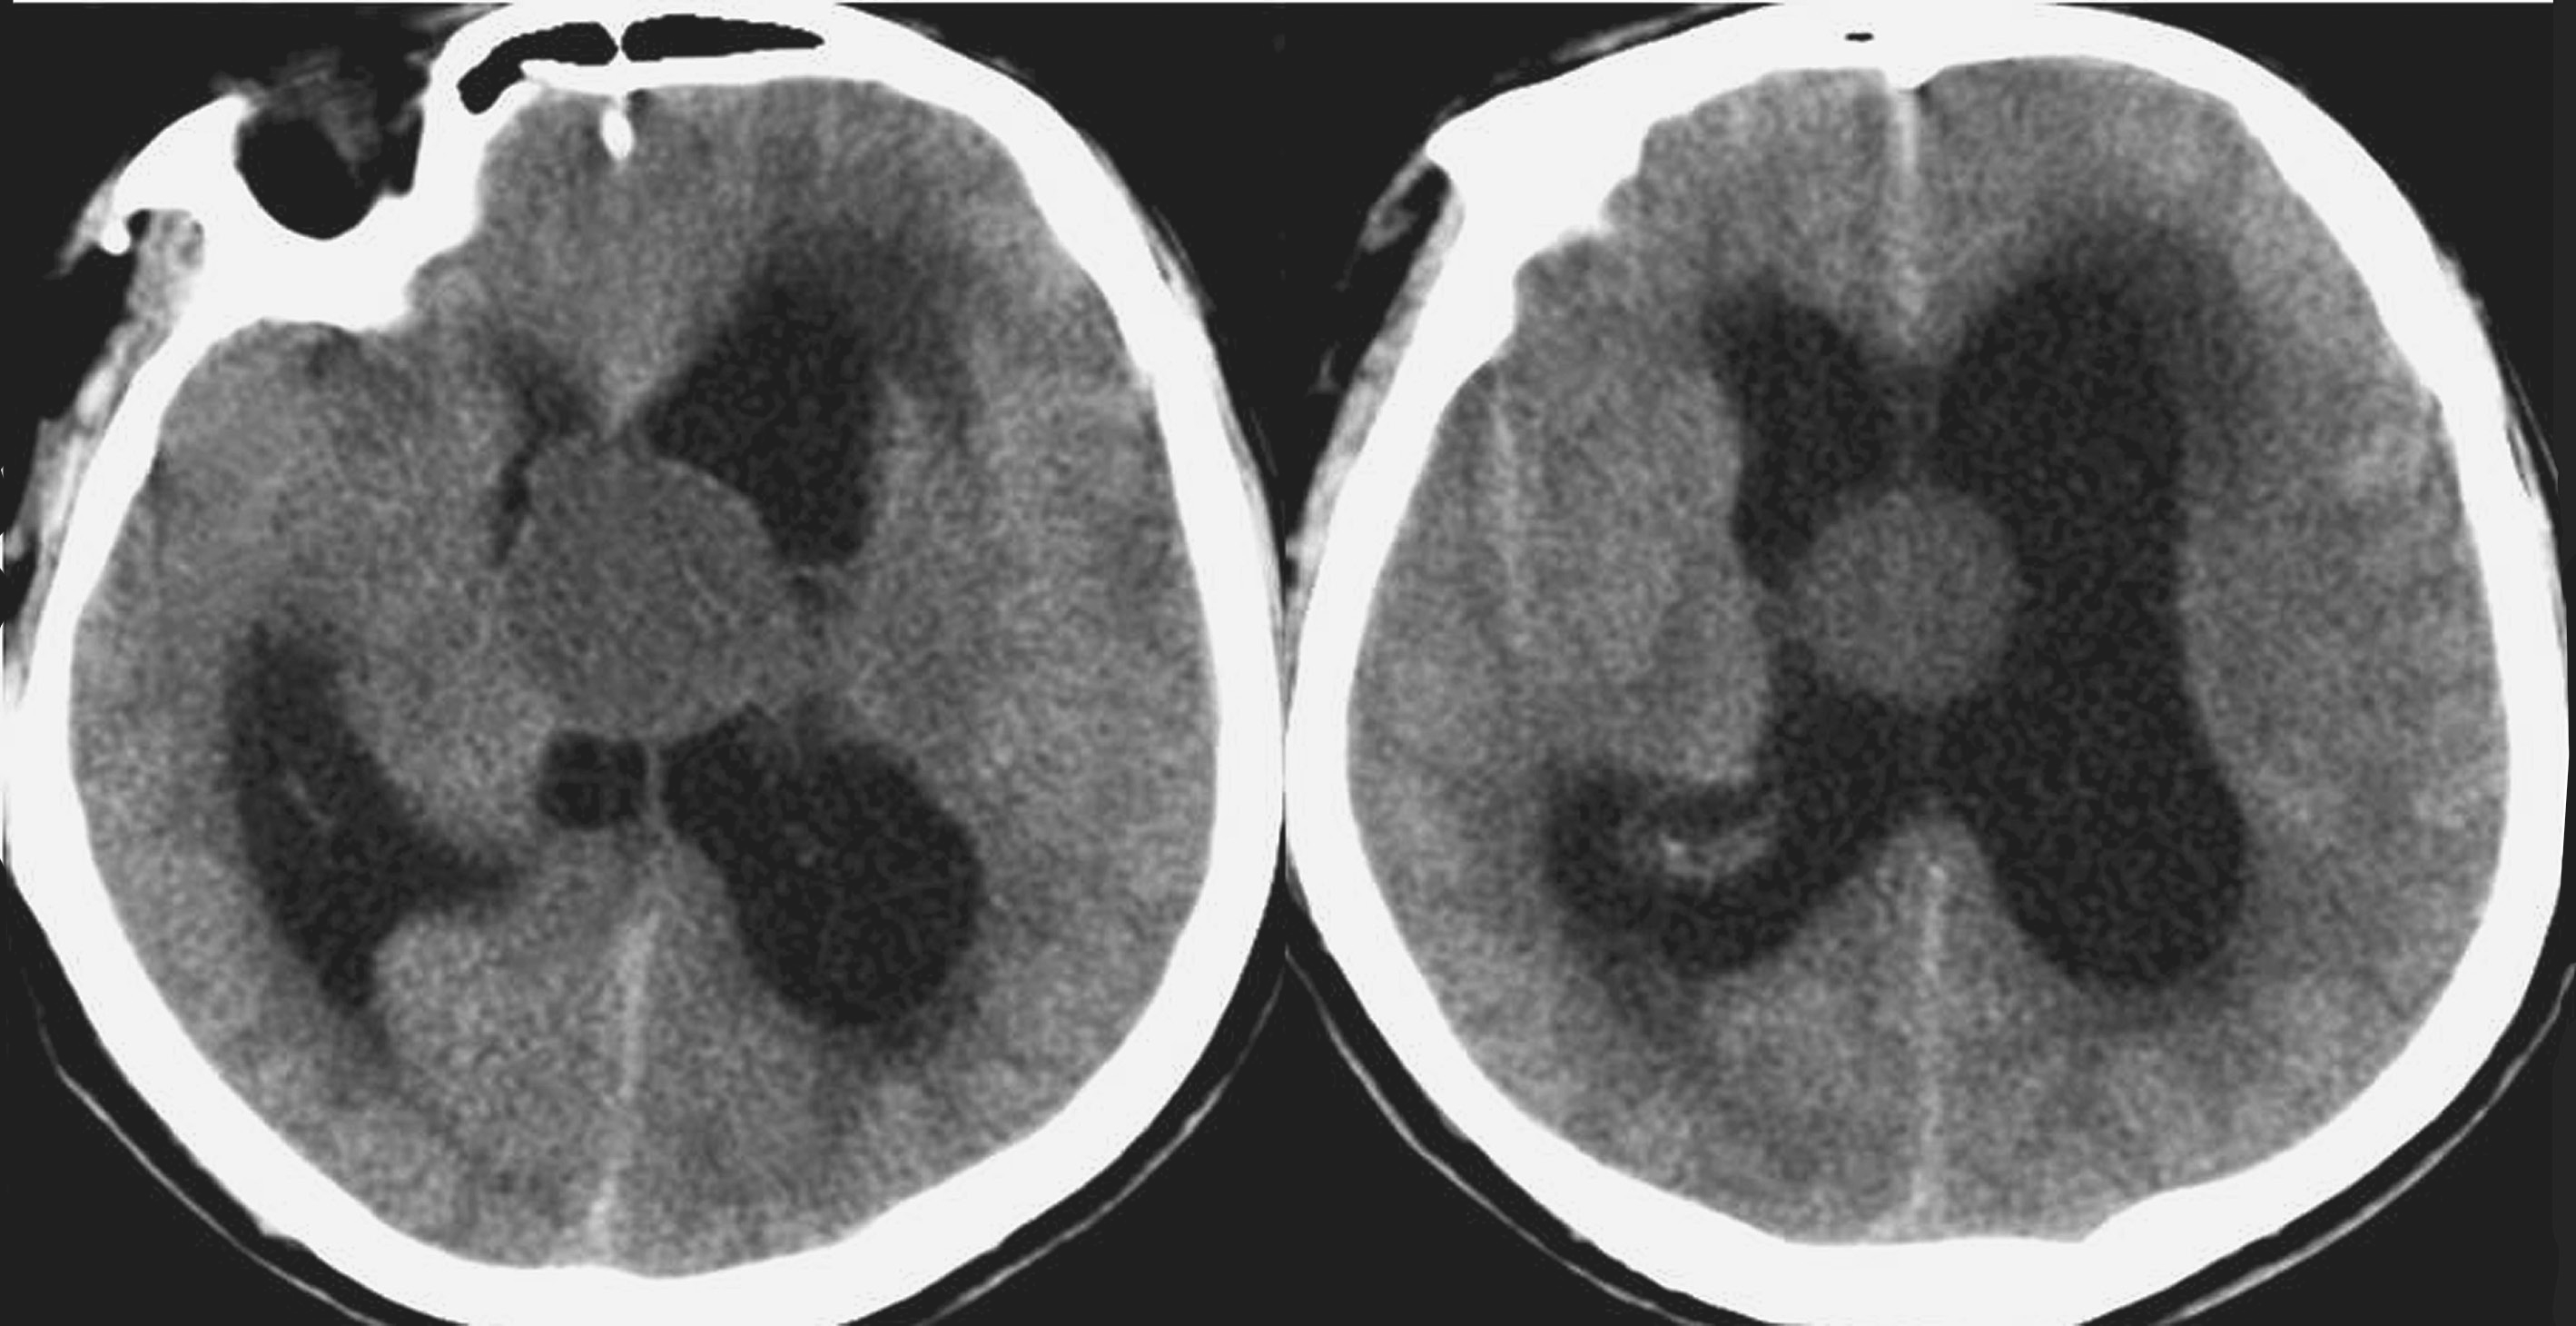

患者,男,58岁,主诉“头痛半年,突发抽搐伴昏迷10小时”。

现病史:患者半年前无明显诱因出现头痛,为双颞侧胀痛,能自行缓解,未予特殊诊治。近1个月来患者头痛症状明显加重,伴有呕吐,于当地诊所静脉滴注甘露醇注射液治疗有效。10小时前患者排尿后突发抽搐2次,表现为神志不清、四肢痉挛、口吐白沫,每次持续约30秒。于当地医院行头颅CT检查显示颅内占位病变伴脑积水,镇静、脱水治疗后未再有抽搐发作,为求进一步治疗急诊转来医院。

查体:嗜睡状态,查体不配合。双瞳孔等大正圆,直径约4.0mm,对光反射迟钝,无眼球震颤或斜视;颈强直;心肺未闻及异常;腹平软,无肌紧张;四肢刺痛有躲避反应,肌张力增高。膝反射亢进;双侧征阴性。

辅助检查:头颅CT(图5-1-3)提示第三脑室见类圆形低密度病变,脑室普遍扩大,脑沟消失,伴侧脑室周围低密度水肿带。

图5-1-3 头颅CT表现

初步诊断:第三脑室内占位性病变;高压力性脑积水。

治疗过程:双侧侧脑室外引流术。